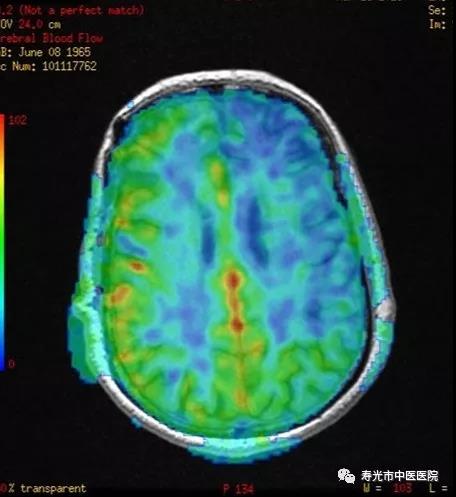

3.0T静音超导高端核磁共振还有一个优势是脑动脉自旋标记灌注成像(ASL),这是一种不使用造影剂而获得脑灌注成像的方法,显示血管形态和周围病灶清楚,具备无创、成本低、安全性高、操作简单、可重复检查等优点。

烟雾病颅骨多点钻孔术后脑灌注效果评估